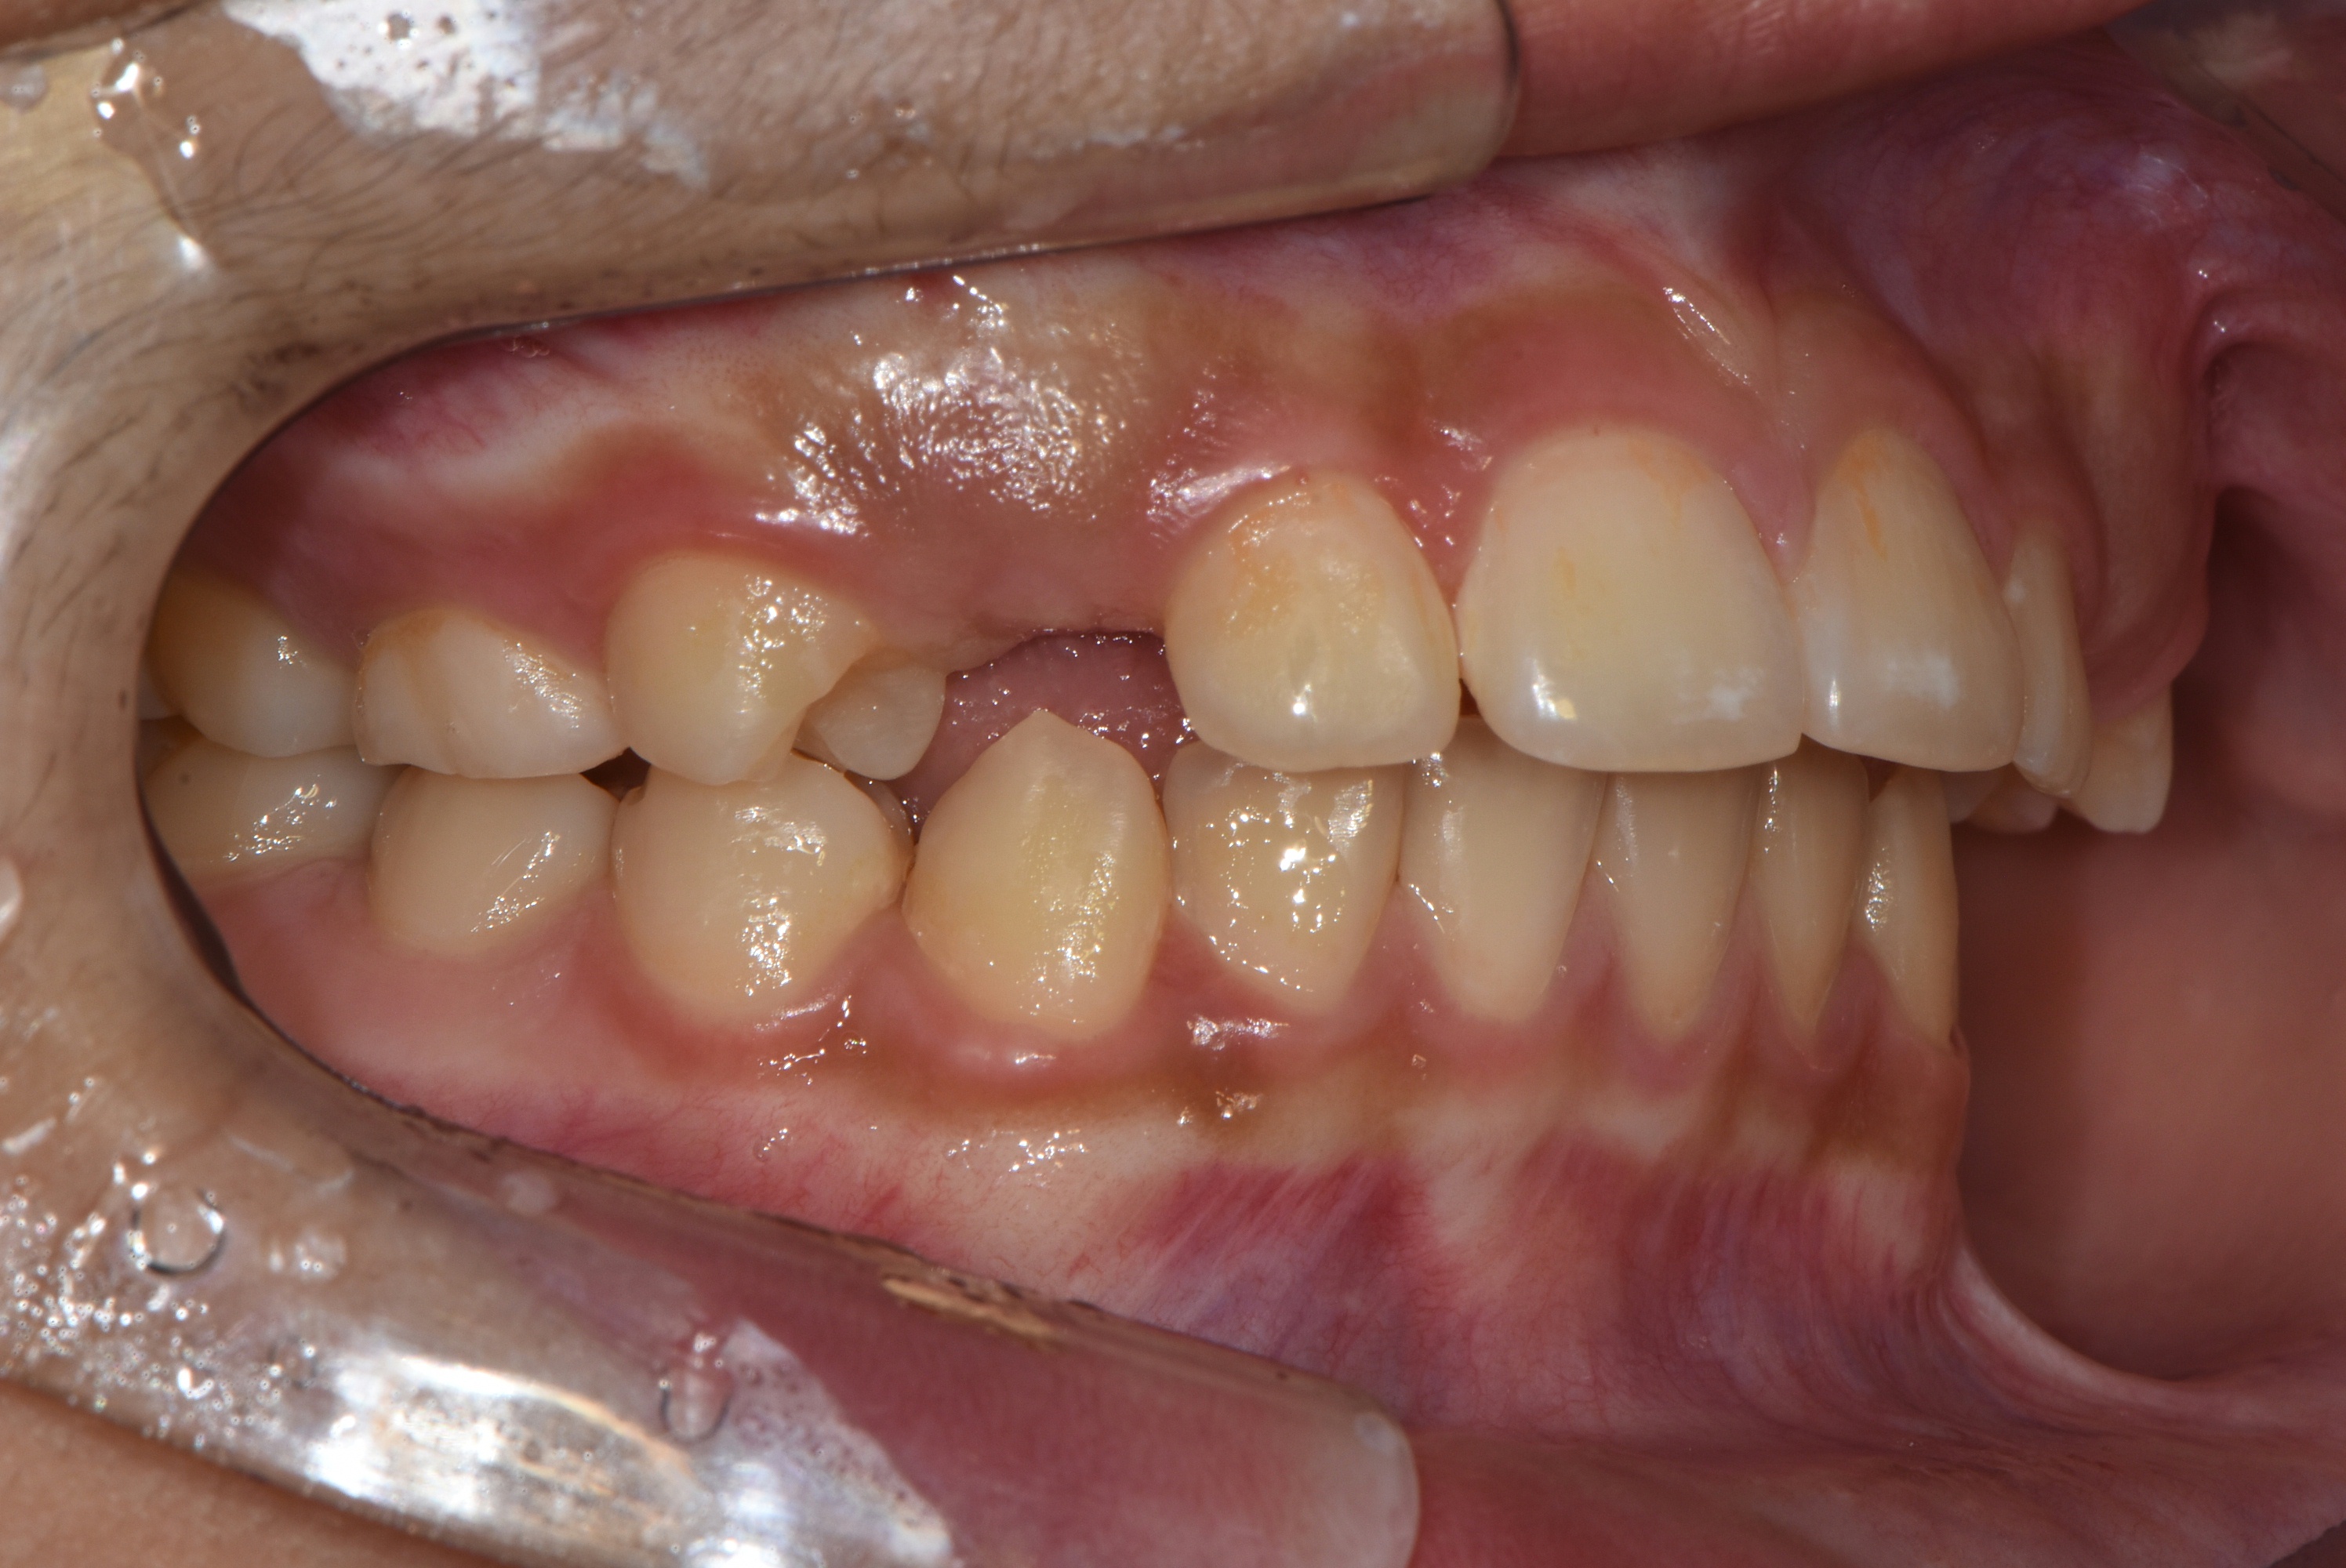

치료 전 사진입니다.